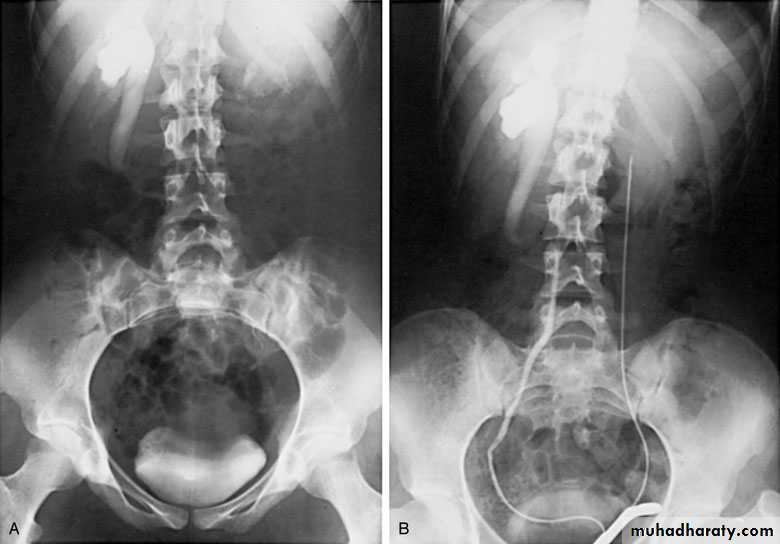

Ureteropelvic Junction (UPJ)(PUJ) Obstruction (stenosis)

The most common cause of significant dilation of the collecting system in the fetal kidney

Boys > Girls

Left-sided lesions predominate

15% bilateral

DIAGNOSIS

U/S: hydronephrosis

IVU: diagnostic , hydronephrosis with

fixed stenotic segment or complete

obstruction

CT scan: hydronephrosis that ends

abruptly

Treatment:

Medical: control infection and pain.

Surgical:

Indications for surgery:

1-progressive hydronephrosis.

2- UTI, and symptomatic patients.

3- Severe hydronephrotic non functioning kidney.

Treatment

SURGICAL REPAIR including open surgical techniques, laparoscopic, & endoscopic approaches

Open & laparoscopic surgical techniques Anderson-Hynes dismembered pyeloplasty:

excision of the pathologic UPJ & appropriate

reanastamosis or flap technique or flap

operation

Bilateral PUJO